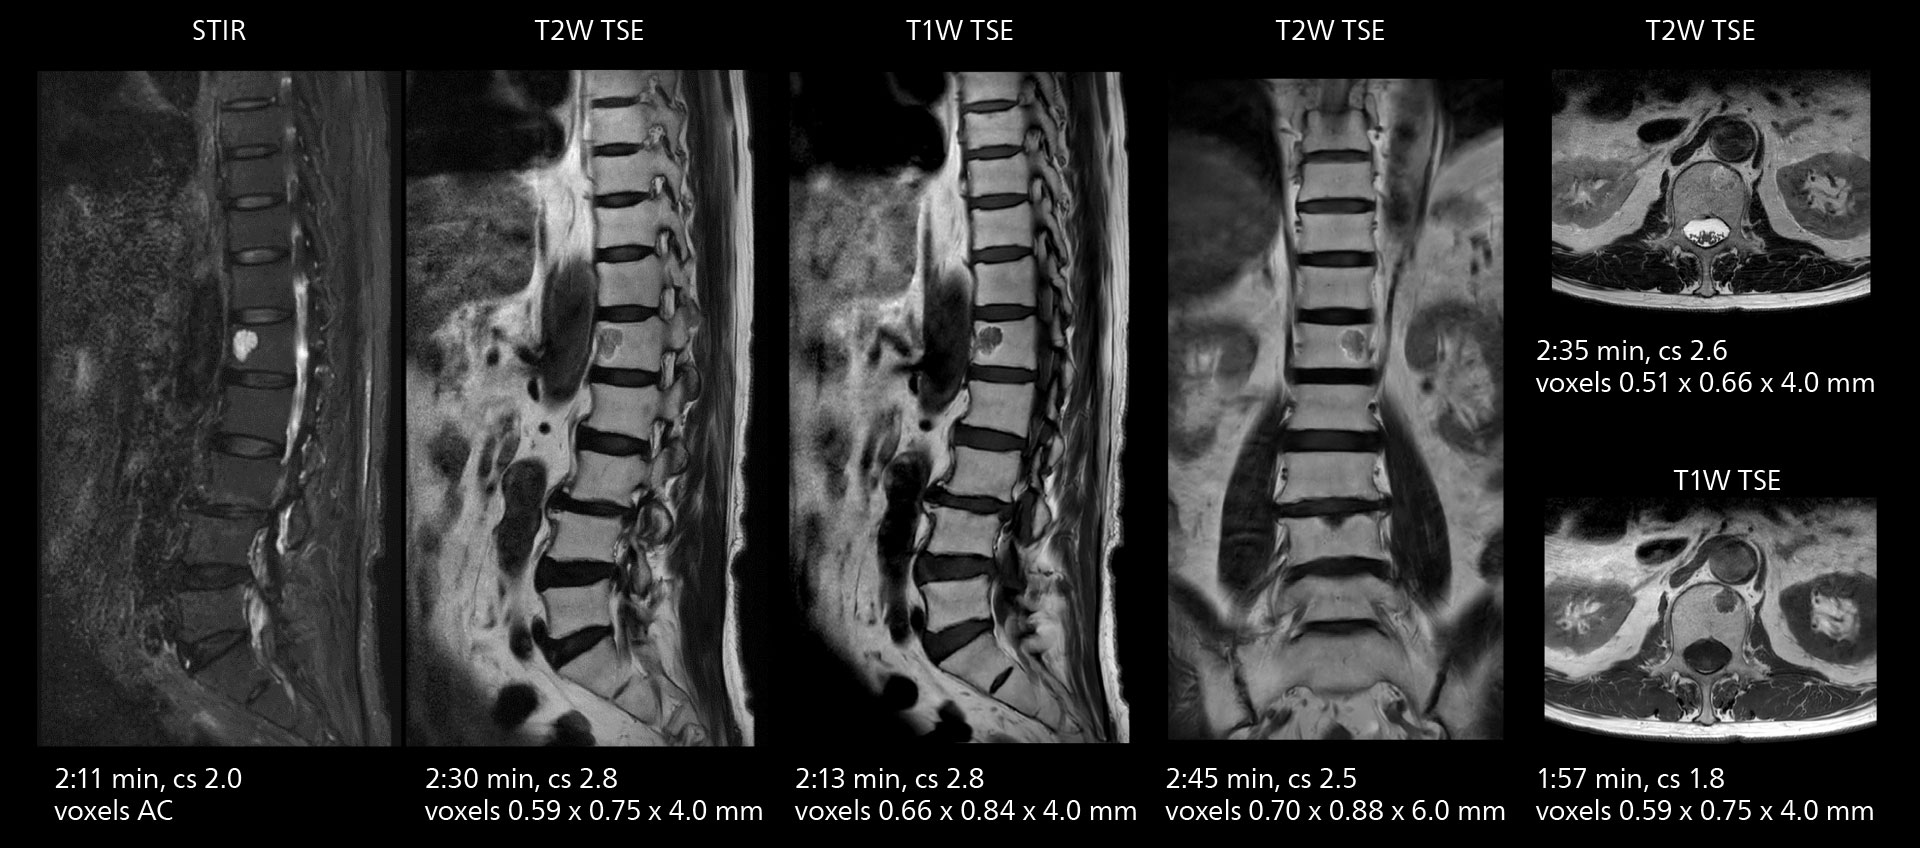

Lumbar spine MRI

Crisp images are obtained with high resolution and short scan times using Elition X. A cyst can be seen.